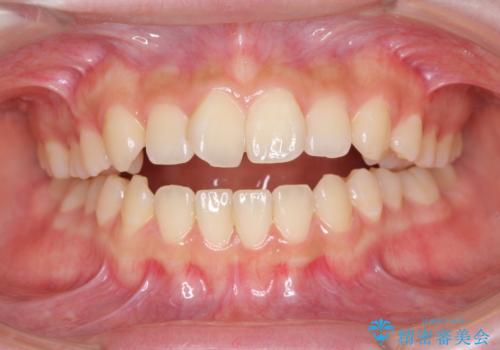

上下前歯が接触しない オープンバイトをインビザラインで改善

オープンバイト(開咬)を非抜歯インビザラインで治す